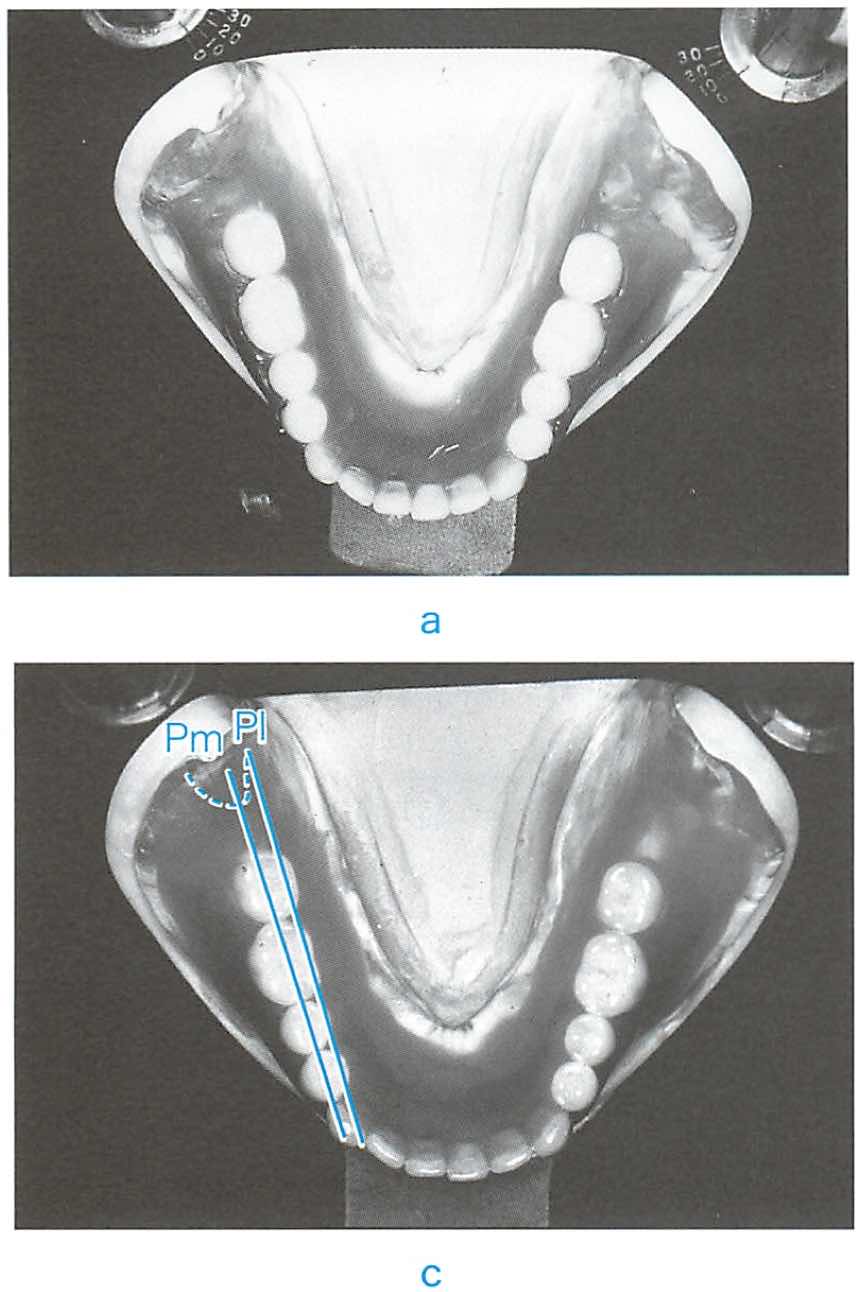

26歳の女性。上顎左側小臼歯部の食片圧入を主訴として来院した。上顎左側5に自発痛はなく,歯髄電気診に反応する。コンポジットレジン修復を行うこととした。初診時の口腔内写真とエックス線写真とを別に示す。爾窩の開拡にあたって必要な前準備はどれか。2つ選べ。

スクリーンショット 2017 01 18 1 19 46

a 隔壁

b 咬合調整

c 歯肉圧排

d 歯間分離

e ラバーダム防湿

正答 d e

ややこしいですが、削るときの隔壁も必要な気がします。でも、それ以上に「ラバーダム」は必須ですし、歯間離開は絶対的に重要です。その上でさらに削らないように隔壁を立てると安全になりますが、必須ではありません。3つ選べであれば、a, d, eが正答になっていたでしょう。